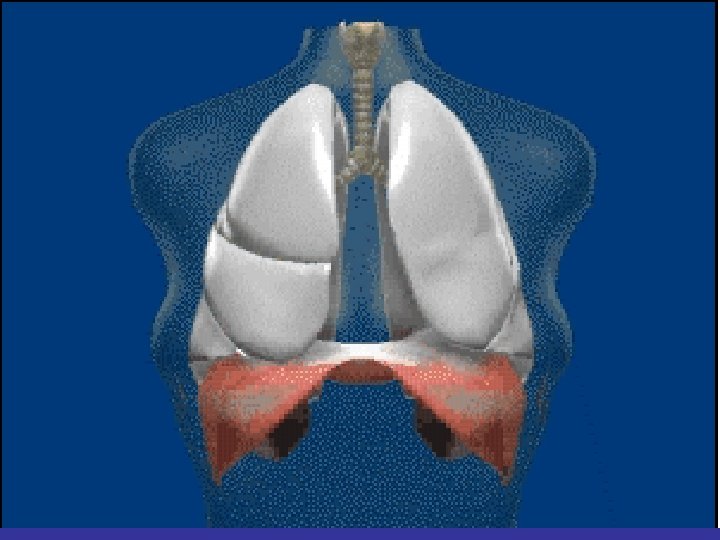

Lobes and Fissures